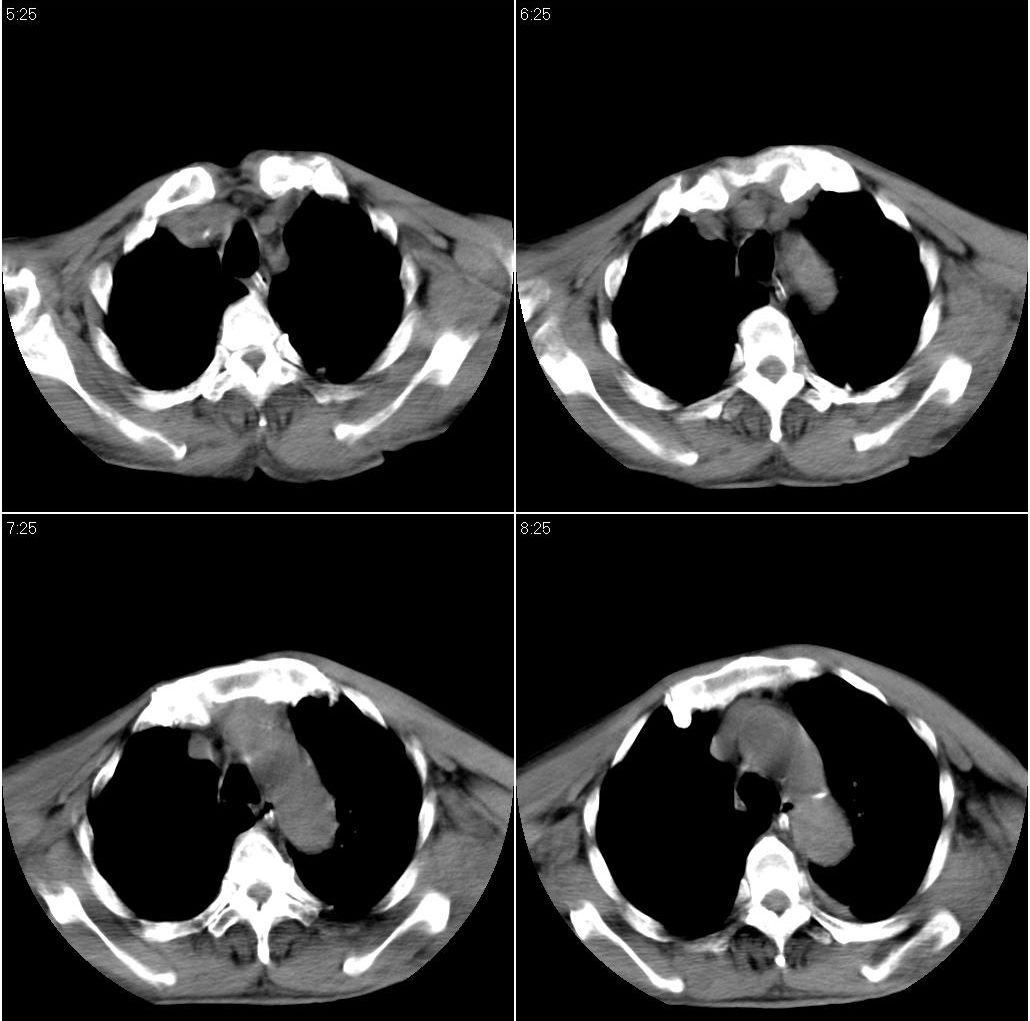

男性,65岁。因外伤来诊。该患者因脑外伤住院。以下是今天的dr和ct:

以下是一周前外伤时的dr:

1 外伤性左侧膈疝、胸腔积液致左肺下叶不张 2右肺挫伤

右侧第7肋骨腋段骨折并右肺挫伤;左侧膈疝并肺不张。

1 左下肺压迫性肺不张拌血胸

2 右侧肋骨骨折伴右肺挫裂伤